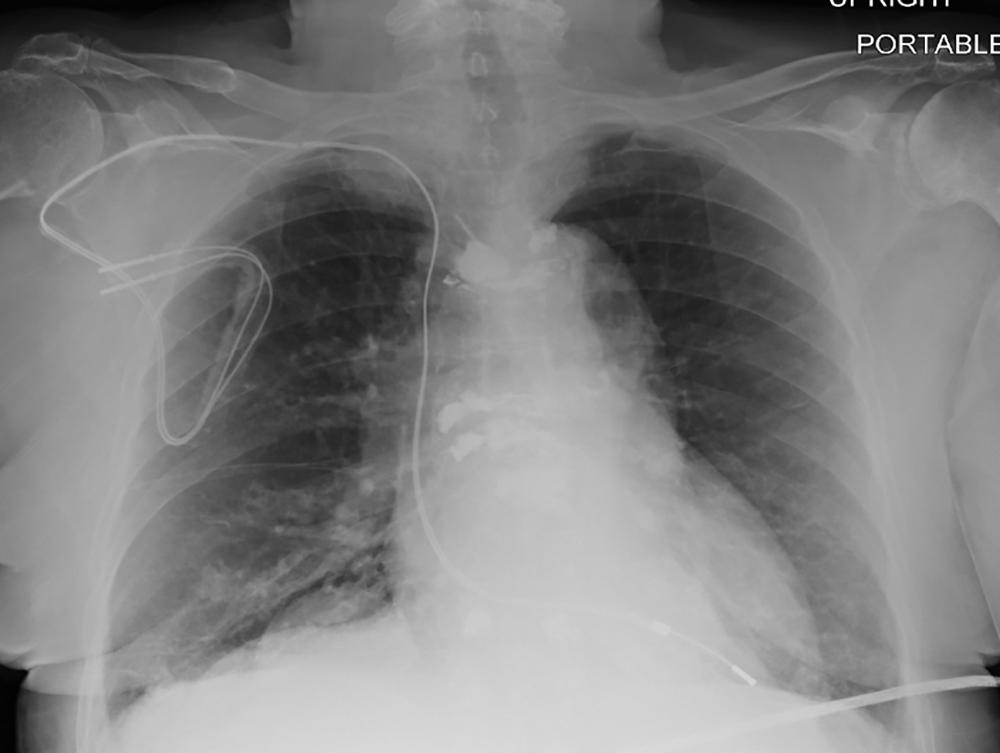

Figure 4. Chest radiograph, posteroanterior view, in a 64-year-old woman with history of heart transplantation, demonstrates retained portion of right ventricular pacing lead and defibrillator lead with superior vena cava coil. This patient underwent five MRI examinations as part of this registry.